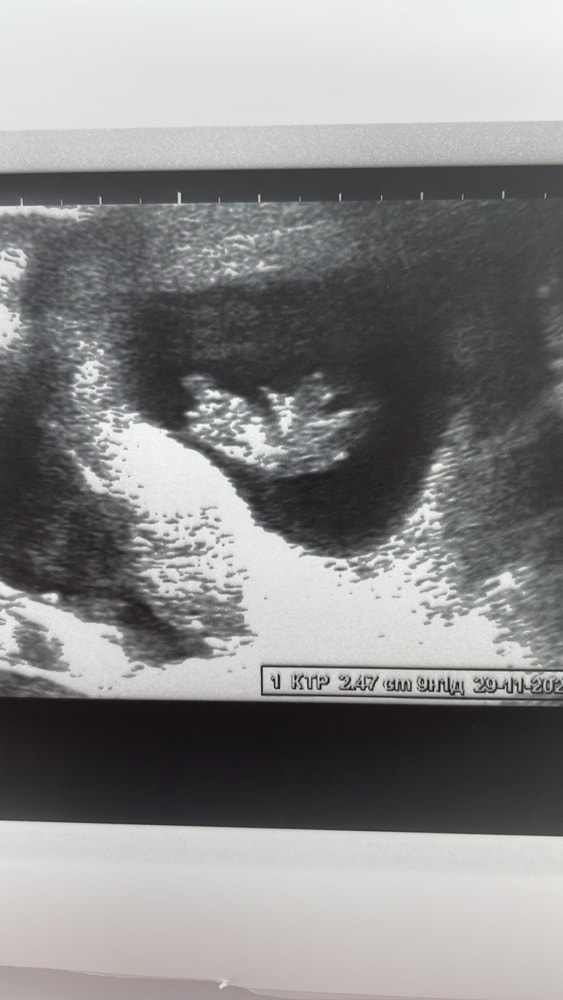

как все интересно начиналось. Тренировочные схватки, потом вроде как пробка… через 8 часов от первого куска пробки поехали в роддом, схватки становились ярче. Подключили ктг и тут лопнул